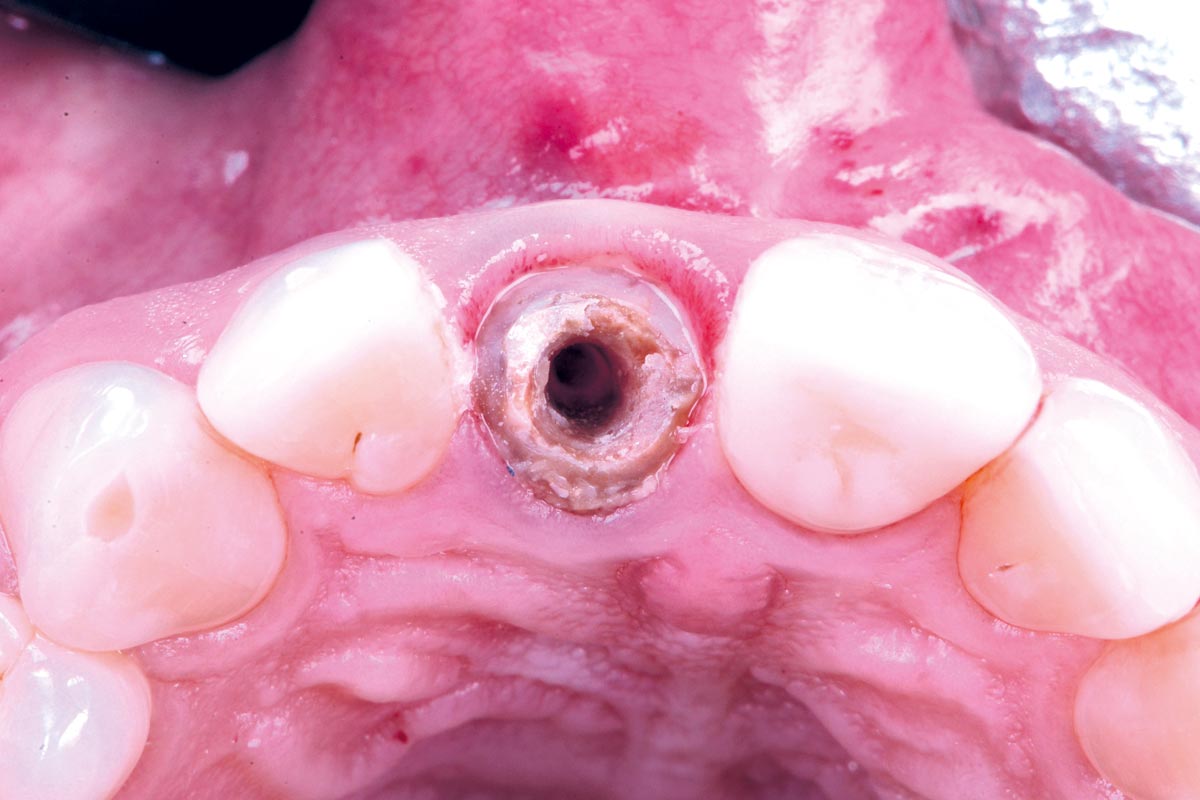

11/30 - Bone profiler was used to remove supracrestal boneExcellent aesthetic result of buccal augmentation with mucoderm® and maxgraft® after immediate implant placement - 3-years follow-up - Dr. A. Puišys